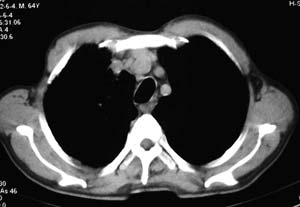

右侧胸廓略小于左侧,右肺上叶大片实变影,近肺门处密度较高,内见支气管气相,周围较淡,呈网格状,余肺野清晰,纵隔内见肿大淋巴结,右侧胸腔少量积液。临床 咳血,咳痰 发热 , 血象1.2万。

考虑大叶性肺炎。

病史:男 64  咳血,咳痰 发热 3天 血象1.2万。

影像表现:肺窗示右肺上中叶均可见小片、条索状、小结状密度增高影,可见支气管充气相,小叶间隔增厚,支气管通畅,余肺未见明显异常。纵隔窗示4r可见小淋巴结融合,无明显肿大,右侧示少量胸腔积液。

诊断:提示右肺上中叶感染性病变,tb可能大。

右侧胸阔塌陷,纵隔右移。右上肺大片状高密度影,沿支气管血管束走行,内见点状钙化;支气管充气征阳性,支气管呈柱状扩张;胸膜下小叶间隔增厚;右侧后胸壁内侧见带状水样密度影;纵隔淋巴结增大。

考虑:①右上叶陈旧性结核合并感染可能大。②右侧少量胸水。